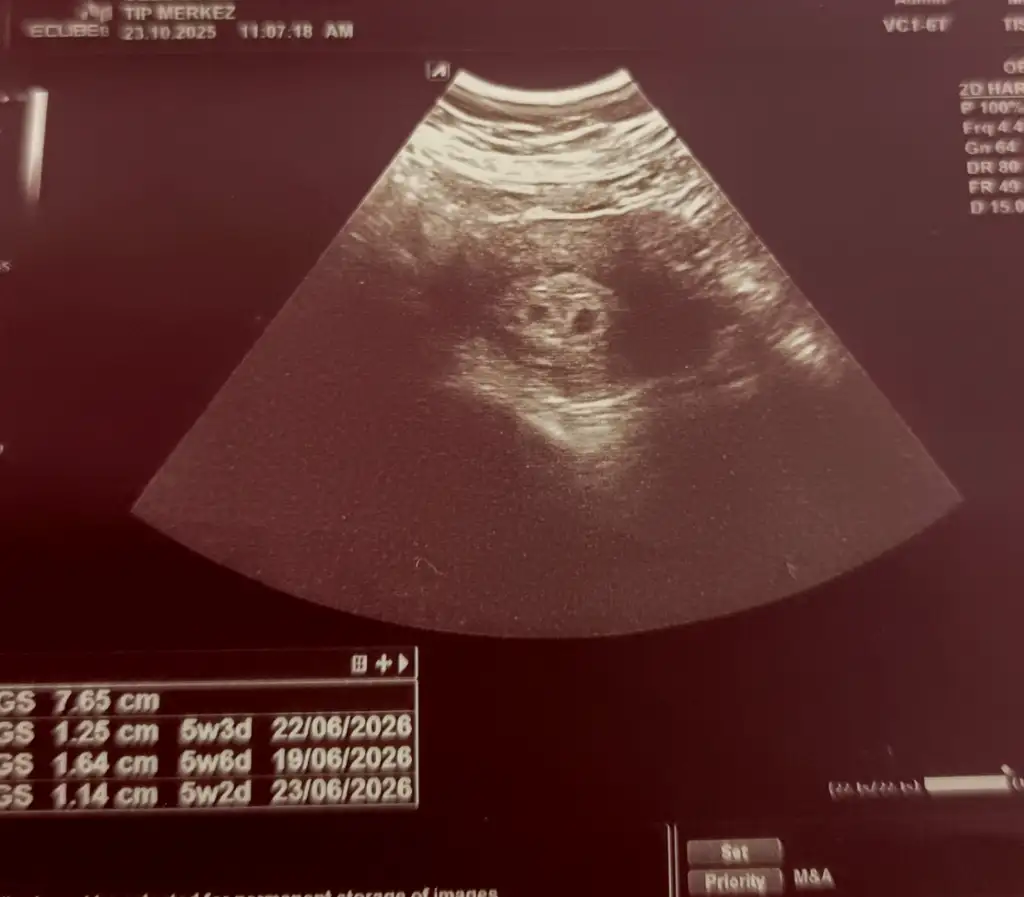

Perşembe günü saat 1 e kese randevusu aldık başka bir doktordan. Ama ben panikten dayanamadım. Ve bugün bir çılgınlık yapıp yine kan verdim.

Şimdi cumartesi günü 1586 olan Beta 3 gün sonra şimdi 9723 geldi 🥰🧿🧿🧿

Acaba ikiz olabilir mi? Kafamda deli sorular. Yüreğim pır pır 🐦🐦

Rabbim nasip ederse yine ikizlerim olacak 🧿🤲